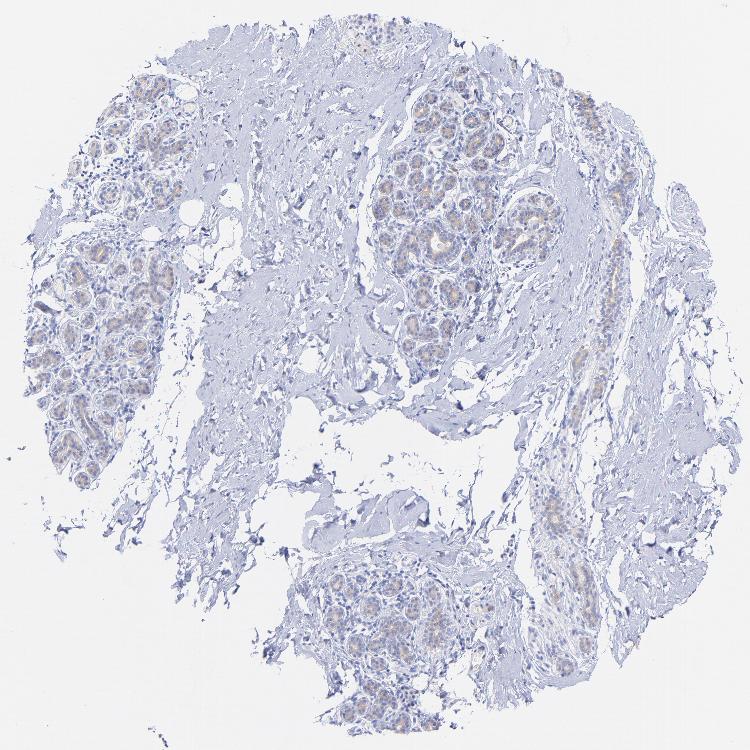

BREAST - Antibody stainingi

Antibody staining in the annotated cell types in the current human tissue is reported as not detected, low, medium, or high, based on conventional immunohistochemistry profiling in selected tissues. This score is based on the combination of the staining intensity and fraction of stained cells.

Each image is clickable and will lead to virtual microscopy that enables deeper exploration of all samples and also displays staining intensity scores, fraction scores and subcellular localization as well as patient and tissue information for each sample.

Antibody HPA003116Antibody HPA024694Antibody CAB004419

Adipocytes Not detectedNot detectedNot detected

Glandular cells LowNot detectedHigh